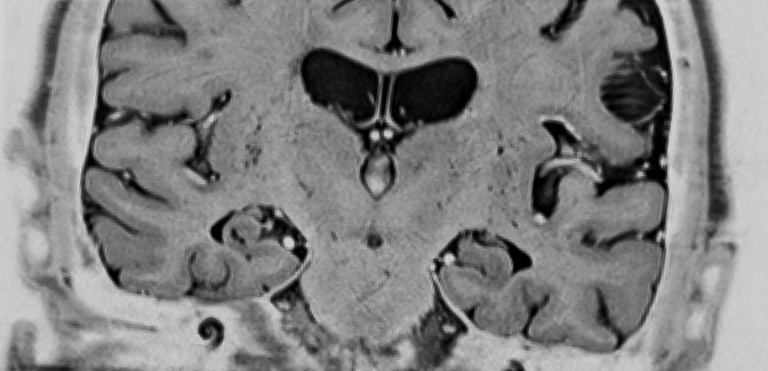

This is a coronal view of the hippocampus brain region of a patient with Alzheimer’s disease. Image courtesy of Daniel Tranel's Laboratory at the UI's Department of Neurology.